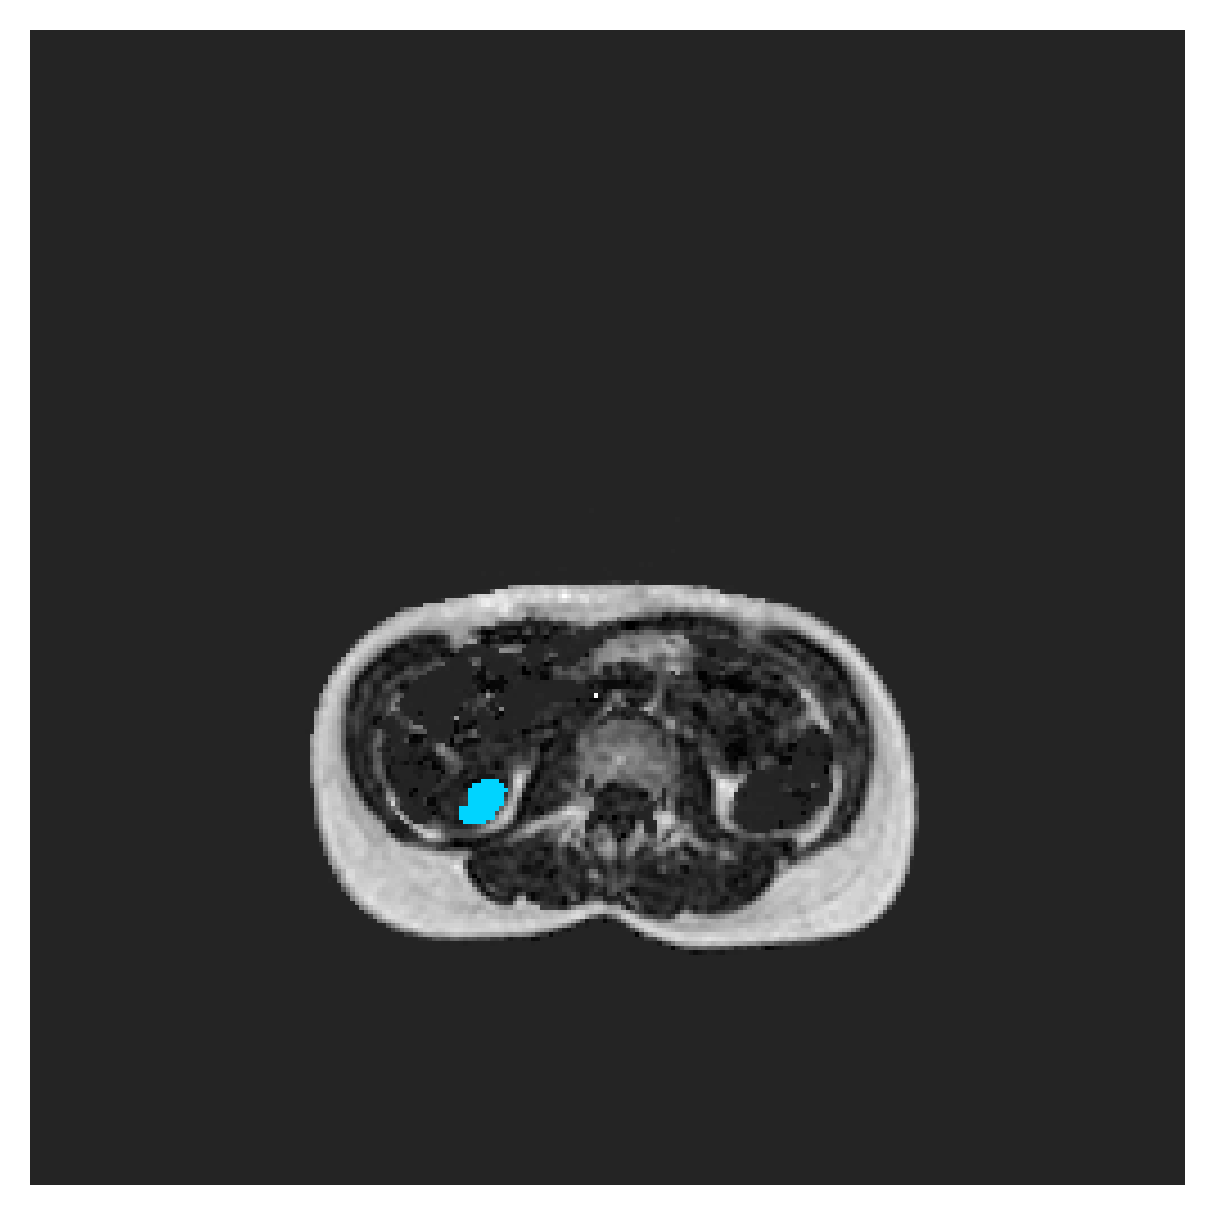

POEM

The Prospective investigation of Obesity, ENergy production and Metabolism (POEM) is a local (not currently publicly available; PI: L. Lind, see [22] for details) cohort of whole-body fat/water separated MR images. Full annotations of the liver, kidneys, bladder, pancreas and spleen are available for 50 subjects, providing a challenging segmentation dataset with heavily imbalanced classes of varying shapes. The resolution of the data is anisotropic, with reconstructed voxel size of in left-right, anterior-posterior and foot-head directions, respectively. For additional technical details regarding the acquisition and specifications of the images see [22].

The images contain two channels, one for water and one for fat content. For training, we normalize the volumes (per channel) and use 2D slices in the coronal plane, sized . The weak annotations are created synthetically, following the same procedure as described for the ACDC dataset.

5.2 Abdominal organ segmentation

Using 2D distance maps

In Table 3, the average DSC and HD95 results are shown (both using 2D and 3D distance maps) for the task of abdominal organ segmentation in POEM data (for boxplots see figures 8 and 9). We see that training with and (with distances calculated on 2D slices) performs comparably, while using and produces lower scores in both DSC and HD95 metric. On this dataset, the CRF-loss is able to compete with the boundary loss-based training strategies, even outperforming them on most classes. Most notably, all models trained with boundary loss appear to have a hard time segmenting the liver. We hypothesize this may be due to extremely severe class imbalance, as the liver covers a very large area compared to the rest of the classes. It is thus also more strongly affected by undersegmentations.

Using 3D distance maps

Inspecting the values of training with on distance maps computed in 3D from Table 3, we notice that the results generally improve over values achieved by using 2D distance maps. Most notable decreases are visible in HD95 values, as using volume-calculated distance maps provides more global information and additionally penalizes spatially unreasonable segmentations. The methods based on are now able to compete with the CRF-loss, in particular the one.

In Figure 10, the validation curve evolution is plotted. Comparing it to the one with using 2D-computed distance maps, in Figure 7, we see that the curves for all the methods training with improve, with the exception of based one. The lack of improvement here could be attributed to the MBD bleeding through object boundaries (due to noise) and propagating low distances further away in the volume, causing under-penalization. This is also suggested by the degradation in performance from 2D to 3D maps in Table 3. But at the same time, it allows for better segmentation of large and/or elongated (homogeneous) objects, which is also confirmed by the large improvement of liver segmentation scores in Table 3.

5.2.1 Qualitative comparison

In Figure 11 and 12 we show the same random slices in cases of calculating the boundary loss on 2D- and 3D-based distances, respectively. Comparing the two figures again indicates that the intensity-aware distances offer most improvement when calculated in 3D over 2D. The exception here is the MBD, which seems to even slightly degrade for most classes.